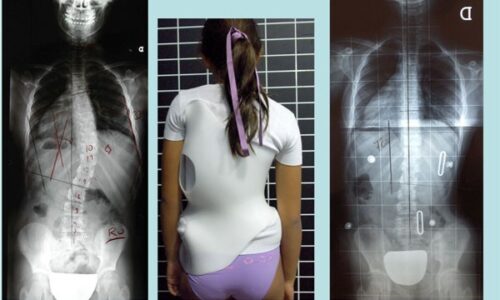

يُعد اعوجاج العمود الفقري (الجنف) من الحالات الشائعة التي تصيب الأطفال والمراهقين خلال مراحل النمو، ويمكن أن تستمر أو تظهر في مرحلة البلوغ. ومن بين العلاجات غير الجراحية الفعالة التي تُستخدم لتقويم العمود الفقري وتقليل تطور الانحناء، يبرز الحزام الطبي أو الجبيرة القطنية كأحد الحلول الأساسية، لكن يبقى السؤال: متى يجب البدء في استخدام الحزام؟ ومتى يكون غير فعال؟

توصي الجمعية الدولية للجنف باستخدام الحزام الطبي في الحالات التالية:

انحناء يتراوح بين 25° و45° لدى المرضى الذين لا يزالون في مرحلة النمو.

حالات الجنف بين 20° و25° عند وجود علامات واضحة لعدم اكتمال النضج الهيكلي (مثل Risser 0 أو Tanner 1-2).

وفي هذه المراحل، يُعتبر الحزام خيارًا فعالًا للحفاظ على استقامة العمود الفقري وتفادي تدهور الحالة.

في كثير من الحالات، نعم. تشير الدراسات إلى أن العلاج بالحزام يقلل من احتمال الحاجة إلى الجراحة، خاصة عند استخدامه مبكرًا مع التزام كامل بخطة العلاج.

استخدم الحزام في حالات الانحناء من 25° إلى 40°، خاصة في مراحل النمو المبكر.

تُظهر الأدلة أن الحزام خيار فعّال وموثوق في علاج اعوجاج العمود الفقري، خاصة في حالات الانحراف القطني والصدري السفلي. كما تُشير النتائج إلى أن الحزام لا يُستخدم فقط لتقويم الانحناء، بل يساهم أيضًا في تحسين التوازن الجسدي والمظهر العام.